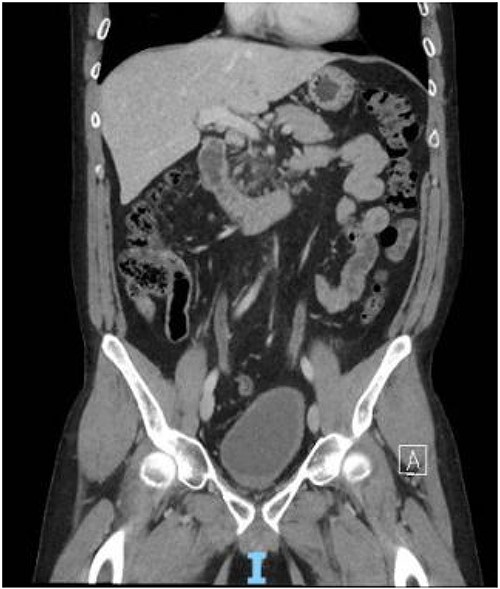

The patient presented to the ED 3 months later with urinary retention and pain; this was relieved with catheterization. A CT scan revealed that his tumor had slightly increased in size (Fig. 1). He had an AUA symptom index of 35. Due to the refractory nature of his obstructive symptoms, he was scheduled for a TURP 2 weeks later, which again revealed leiomyoma. He was kept on interval follow-up for the next 2 years. During that time his PSA was 1.13 ng/ml. Magnetic resonance imaging (MRI) pelvis 2 years later showed the mass appeared to communicate with the posterior bladder neck (Fig. 2). His baseline renal function kept worsening (Creatinine 1.4 mg/dl); at that time, the patient was counseled regarding his treatment options, and he opted for surgery which he was told may require the removal of the prostate with loss of ejaculatory and/or erectile function.

Contrast CT pelvis (May 2020) showing stable complex solid and cystic pelvic mass abutting displacing the bladder superiorly and the prostate laterally.